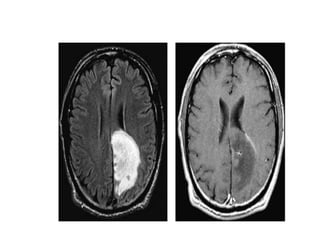

• TYpical findings for MS as seen

in this case are:

• Multiple lesions adjacent to

the ventricles (red arrow).

• Ovoid lesions perpendicular to

the ventricles (yellow arrow).

• Multiple lesions in brainstem

and cerebellum.

• These ovoid lesions are also

called Dawson fingers.

They represent areas of

demyelination along the small

cerebral veins that run

perpendicular to the

ventricles.